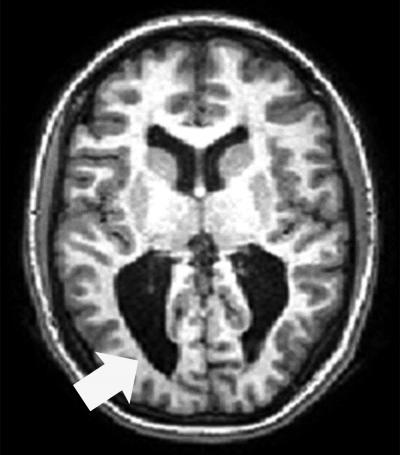

Cross-section of fMRI brain scan with arrow pointing to dark area

Magnetic resonance imaging scan shows an adolescent with CVI associated with prematurity. Enlarged ventricles with irregular sulcal patterns (folds) in the occipital pole (a hallmark sign of periventricular leukomalacia, PVL) are apparent (arrow). Credit: Lotfi Merabet

Complications from premature birth are one of the leading causes of CVI. During the second half of pregnancy the brain is rapidly developing, making it particularly vulnerable to certain types of injury such as periventricular leukomalacia (PVL). PVL is associated with damage to the developing neurons and support cells in many parts of the brain, especially in areas responsible for motor function and visual processing. As a result, infants with PVL have a higher likelihood of developing cerebral palsy and CVI.